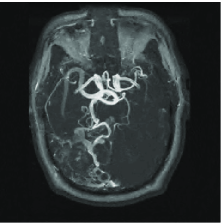

Compressed sensing can help reduce the scan time in Magnetic Resonance Imaging (MRI) and offer sharper images of living tissues. This is especially important because time consuming MRI scans have traditionally limited the use of this sensing modality in important applications. Simply put, faster imaging here means novel applications. In MR, one collects information about an object by measuring its Fourier coefficients and faster acquisition here means fewer measurements.

We mimic an MR experiment by taking our unknown image to be the pixel MR angiogram image shown in Figure 12(a). We sample the image along 80 lines in the Fourier domain (see Figure 12(b)), effectively taking real-valued measurements . In plain terms, we undersample by a factor of about 3.

Figure 12(c) shows the minimum energy reconstruction which solves

| (18) |

Figure 12(d) shows the result of TV minimization. The minimum -analysis (17) solution where is a three-scale redundant D4 wavelet dictionary that is times overcomplete, is shown on Figure 12(e). Figure 12(f) shows the result of reweighting the analysis with and set to 100. For a point of comparison, the maximum wavelet coefficient has amplitude 4020, and approximately 108000 coefficients (out of 655360) have amplitude greater than 100.

We can reinterpret these results by comparing the reconstruction quality to the best -term approximation to the image in a nonredundant wavelet dictionary. For example, an reconstruction error equivalent to the reconstruction of Figure 12(c) would require keeping the largest wavelet coefficients from the orthogonal wavelet transform of our test image. In this sense, the requisite oversampling factor can be thought of as being . Of course this can be substantially improved by encouraging sparsity, and the factor is reduced to using TV minimization, to using analysis, and to using reweighted analysis.

We would like to be clear about what this means. Consider the image in Figure 12(a) and its best -term wavelet approximation with ; that is, the approximation obtained by computing all the D4 wavelet coefficients and retaining the largest in the expansion of the object (and throwing out the others). Then we have shown that the image obtained by measuring real-valued Fourier measurements and solving the iterative reweighted analysis has just about the same accuracy. That is, the oversampling factor needed to obtain an image of the same quality as if one knew ahead of time the locations of the most significant pieces of information and their value, is just 3.